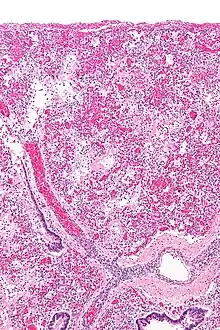

ARDS is a form of fluid accumulation in the lungs not explained by heart failure (noncardiogenic pulmonary edema). It is typically provoked by an acute injury to the lungs that results in flooding of the lungs' microscopic air sacs responsible for the exchange of gases such as oxygen and carbon dioxide with capillaries in the lungs.[12] Additional common findings in ARDS include partial collapse of the lungs (atelectasis) and low levels of oxygen in the blood (hypoxemia). The clinical syndrome is associated with pathological findings including pneumonia, eosinophilic pneumonia, cryptogenic organizing pneumonia, acute fibrinous organizing pneumonia, and diffuse alveolar damage (DAD). Of these, the pathology most commonly associated with ARDS is DAD, which is characterized by a diffuse inflammation of lung tissue. The triggering insult to the tissue usually results in an initial release of chemical signals and other inflammatory mediators secreted by local epithelial and endothelial cells.

Neutrophils and some T-lymphocytes quickly migrate into the inflamed lung tissue and contribute in the amplification of the phenomenon. Typical histological presentation involves diffuse alveolar damage and hyaline membrane formation in alveolar walls. Although the triggering mechanisms are not completely understood, recent research has examined the role of inflammation and mechanical stress.